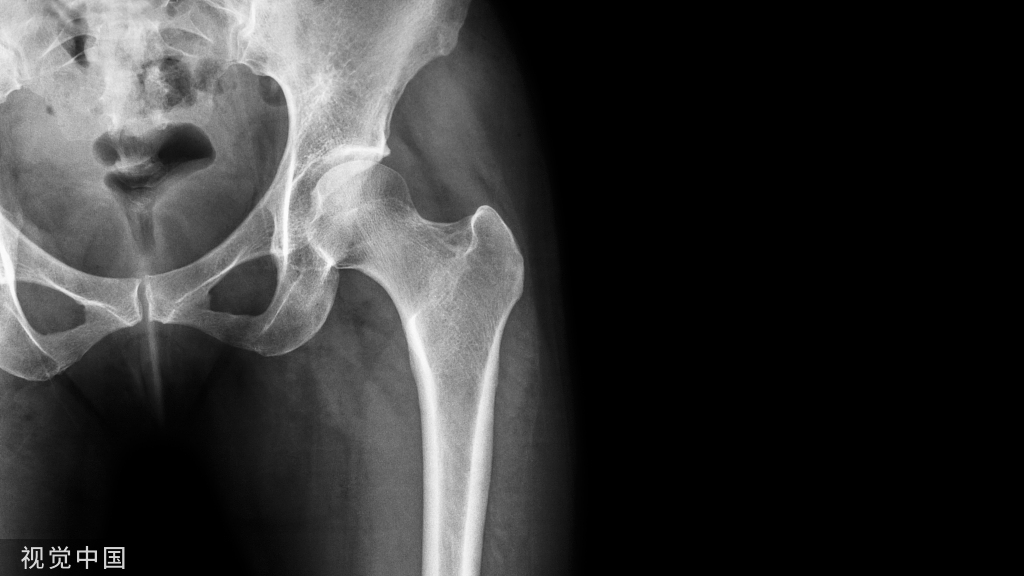

膝关节内翻畸形,首先做伸直位的平衡,然后再通过股骨假体适当的旋转获得屈曲位的平衡。股骨旋转的基本参数可以通过 Whiteside线、经股骨髁上轴线及基于股骨后髁的3°外旋联线等确定。

屈膝90°,用间隔垫片插入,测试屈曲间隙。膝内翻严重时,股骨内髁常增生,需增加外旋。

以Whiteside线确定股骨假体旋转程度,安放截骨导向板,外侧钉孔放于原先的位置,内侧钉孔抬高,使两钉孔连线与胫骨截骨面平行。